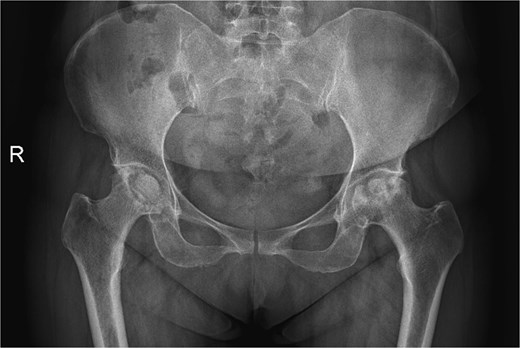

A 47-year-old woman, weighing 65 kg with a height of 158 cm and a body mass index (BMI) of 26 kg/m2, came to our hospital with chief complaints of bilateral hip pain and difficulty walking for 1 year and underwent left THA and 1 week of right THA because of bilateral avascular necrosis and collapse. X-ray of the pelvis of both hips revealed bilateral avascular necrosis and collapse (Fig. 1). A posterolateral approach was used for the bilateral hips in the lateral decubitus position. The implant consists of a Pinnacle cup (DePuy), DELTA ceramic liner and ceramic femoral head (BIOLOX DELTA), and collarless Corail stem (DePuy). After fixation of the acetabular cup, the senior surgeon placed the ceramic liner into the metal shell by hand. Unfortunately, the liner was not placed in the centre position and became stuck. The edge of the tilted ceramic is slightly greater than the cup, perhaps only 5 mm or less. The surgeon attempted to remove the liner by tamping the edge with the plastic impactor using light force several times, but the process of doing so fractured the ceramic liner (Fig. 2). The alumina ceramic fragment of the liner was removed carefully (Fig. 3), and the site was irrigated well. A 32-mm polyethylene liner and a ceramic femoral head were implanted. Full weight-bearing was allowed on postoperative day 1 with a walking aid. The patient remained hospitalized for 8 days to monitor closely for early perioperative complications. Sutures were removed on the seventh day, and the laboratory results indicated an absence of infection. At the 2-month postoperative interval, the patient achieved a successful outcome, with complete resolution of her preoperative symptoms as well as a return to all her activities of daily living (Fig. 4).